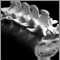

X-ray - lumbosacral spine; X-ray - lower spineDefinition Return to top

A lumbosacral spine x-ray is a picture of the small bones (vertebrae) in the lower part of the spine (the lumbar region) and the sacrum, the area that connects the spine to the pelvis.